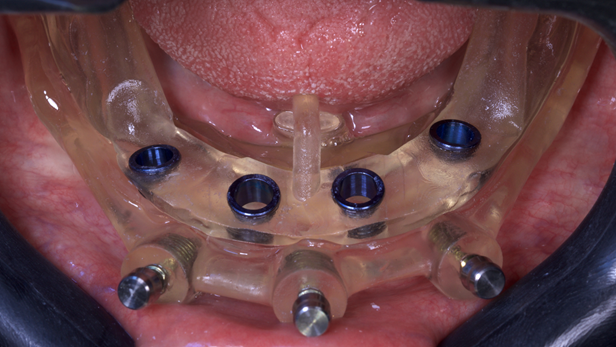

Embora a carga imediata na mandíbula superior esteja amplamente documentada na literatura, relatos sobre osteotomia, instalação e reabilitação de implantes, todos assistidos digitalmente, são escassos. O objetivo deste protocolo totalmente digital é oferecer uma solução eficaz, previsível, com maior precisão, rapidez e com o menor custo possível para o paciente. Para o desenvolvimento deste case, precisávamos de uma guia empilhável. A guia empilhável a ser planejada para transferir intraoralmente o plano virtual para o campo operatório consistia em três componentes:

– guia porta-transporte: toma seu apoio na dentição remanescente e possui uma base de fundação fixada por travas. Sua função é deslocar a base da fundação para seu local exato na boca do paciente;

– base de fundação: fixada ao osso durante todo o tempo da cirurgia por meio de pinos de fixação, possui travas para sua fixação com guias de perfuração posteriores. Também serve como guia de osteotomia;

– guia de perfuração: contém o furo por onde será guiada a broca do implante.

A vantagem desta guia empilhável é que garante uma reprodução exata do que foi planejado digitalmente no computador no campo operatório, proporcionando maior precisão em todas as etapas cirúrgicas. Além disso, facilita o ajuste perfeito da prótese impressa desenhada digitalmente. Para isso, o posicionamento do primeiro guia transportador é de vital importância para o sucesso deste protocolo de reabilitação cirúrgica. É essencial dedicar o tempo necessário para garantir o ajuste perfeito deste guia. Qualquer falha nesta primeira guia afetará a instalação da prótese final. Esta solução de guia empilhável é perfeita para casos complexos que exigem altos níveis de precisão, adaptabilidade e flexibilidade. Um processo abrangente de design digital 3D é usado para criar uma solução eficiente e confiável para procedimentos complexos.